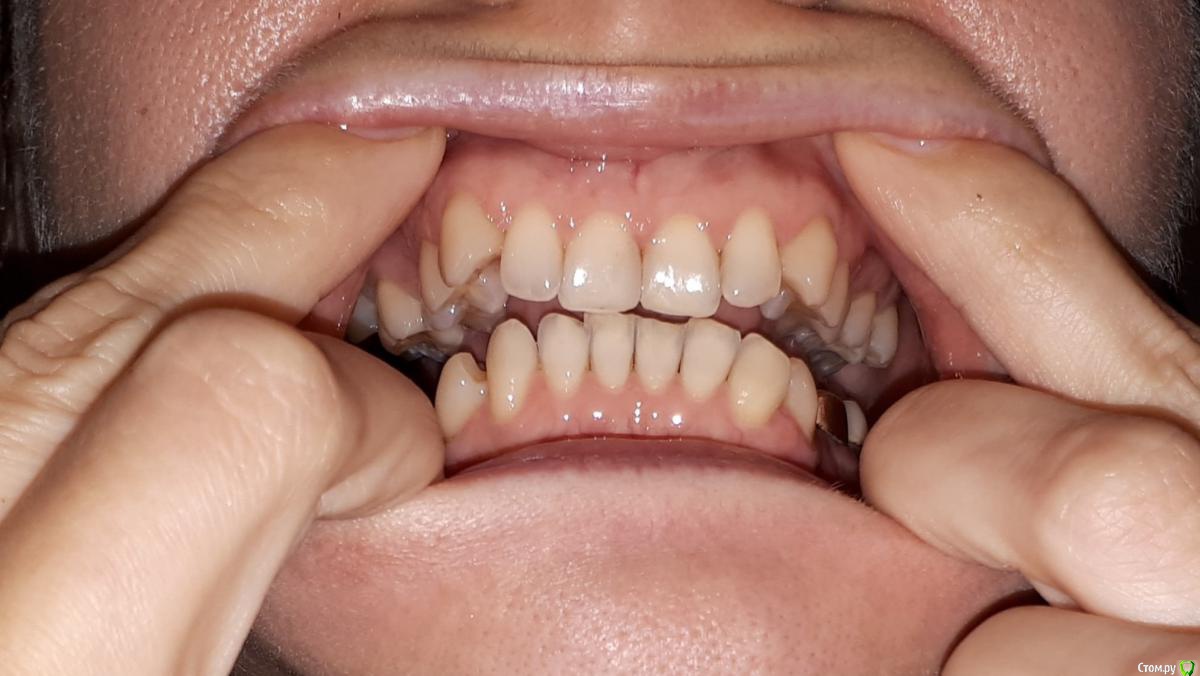

krokomot Опубликовано 17 октября, 2019 Поделиться Опубликовано 17 октября, 2019 сделайте фото передних зубов с десной со вспышкой, попросите кого-нибудь. зубы вы точно не потеряете, но проблемы есть. Ссылка на комментарий

Thunder Опубликовано 21 октября, 2019 Автор Поделиться Опубликовано 21 октября, 2019 сделайте фото передних зубов с десной со вспышкой, попросите кого-нибудь. зубы вы точно не потеряете, но проблемы есть. Ссылка на комментарий

krokomot Опубликовано 21 октября, 2019 Поделиться Опубликовано 21 октября, 2019 Не вижу проблем использовать бреккеты. Атрофии десны нет. Ставте бреккеты и лечите свой прикус. Ссылка на комментарий